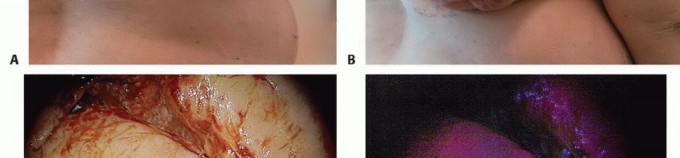

الأعراض والعلامات التحذيرية: متى يجب استشارة الطبيب؟

- التورم أو الكتلة: قد يلاحظ المريض تورمًا أو كتلة محسوسة في المنطقة المصابة. قد تكون هذه الكتلة صلبة أو لينة، وقد تكون مؤلمة عند اللمس أو غير مؤلمة.

من الضروري التأكيد على أن وجود هذه الأعراض لا يعني بالضرورة وجود ورم خبيث، حيث أن العديد من الحالات الحميدة أو الالتهابية قد تسبب أعراضًا مشابهة. ومع ذلك، فإن الاستشارة الطبية الفورية مع أخصائي جراحة العظام والأورام مثل الأستاذ الدكتور محمد هطيف هي الخطوة الأولى والأهم لتشخيص دقيق وتحديد خطة العلاج المناسبة.